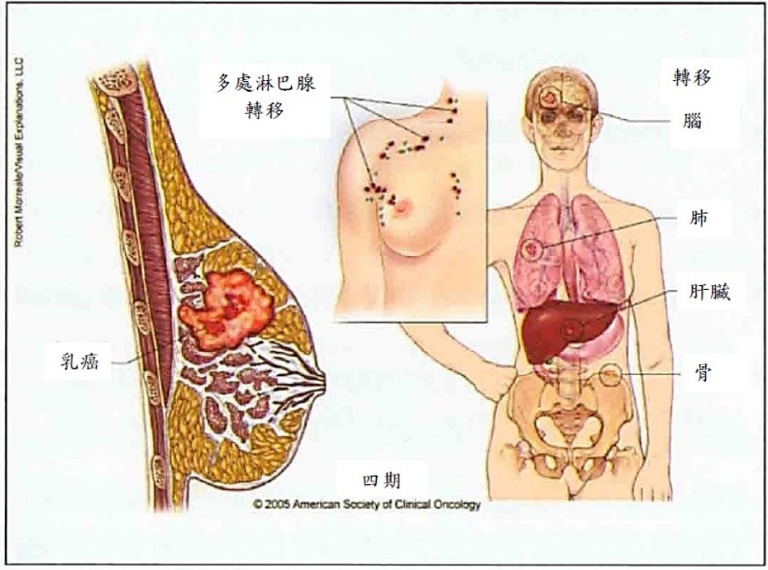

早期乳癌大部分妳都不會有任何症狀或不舒服,尤其零期乳癌(即原位癌) 臨床上常常無任何症狀,但卻以異樣微小鈣化點為表現,在施行乳癌篩檢接受乳房X光攝影時意外早期發現(圖1);等妳發現乳房或腋下有明顯硬塊或腫瘤、乳房變形、乳房皮膚有潰瘍或橘皮狀變化時大多已不是早期乳癌。甚至臨床症狀因骨頭轉移呈現骨頭疼、肺部轉移呈現呼吸困難、肝臟轉移呈現肝機能衰竭、腦部轉移呈現頭痛,神智昏迷時已經是四期乳癌而無法根治痊癒(圖2)。